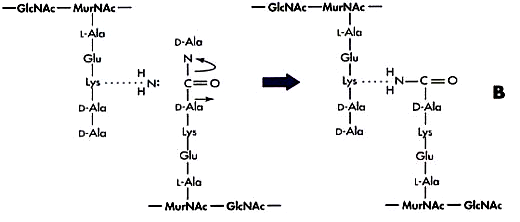

β-lactam

- Penicillin (PCN)

- Cephalosporin

- Carbapenems: Imipenem, Meropenem, Ertapenem

- Monobactam: Aztreonam

機制

Peptidoglycan 形成時 Lys Ala 結合,Penicillin 類似Ala,卡住 Penicillin binding protein (PBPs)

| β-lactam | Penicillin (PCN) | wall | Ala 相似物,競爭PBP結合位 |